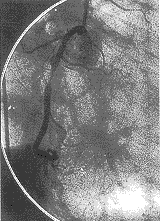

4、冠狀動脈造影 冠狀動脈主要分支有>75%狹窄或左主幹狹窄>50%即可診斷冠心病